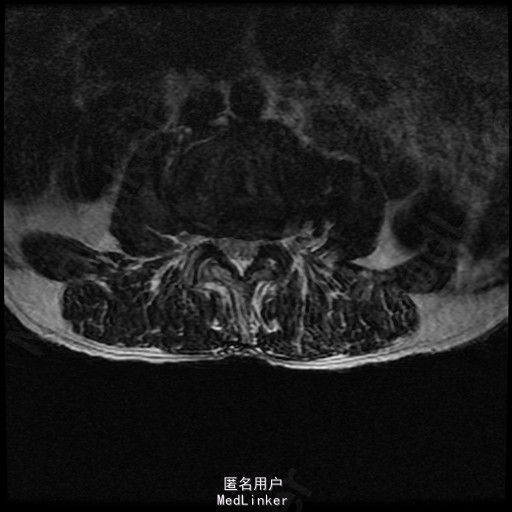

查体:左侧小腿外侧、足背感觉减退,右侧正常,双侧屈髋、伸膝、踝背伸肌肌力5级,左侧踇背伸、跖屈肌肌力4级,右侧踇背伸、跖屈肌肌力4-5级,双侧巴氏征阴性,直腿抬高试验左侧30°阳性,右侧阴性。 辅助检查: X-ray:腰椎退行性变,腰椎节段性性不稳 MR:腰椎间盘突出,腰3/4,4/5,腰4/5节段明显

诊断:腰椎椎管狭窄 处理: 1、完善相关辅助检查,明确诊断,有无手术指证; 2、完善手术评估,有无手术禁忌,手术风险及并发症; 3、在全麻下行腰椎后路减压,腰3/4左侧椎板减压,腰4/5椎间Cage植骨融合内固定术

随访 术后患者下肢麻木感觉较前好转,左侧踝背伸、跖屈肌力4级+,左侧肢体抬高试验阴性。术后MR检查减压彻底 讨论:1、腰椎椎管狭窄手术指证的把握,腰椎后路手术,腰椎椎间融合与椎板减压的选择? 2、术中探查如无明显间盘突出,以椎管骨性狭窄为主,可行腰椎后路椎板减压为主。